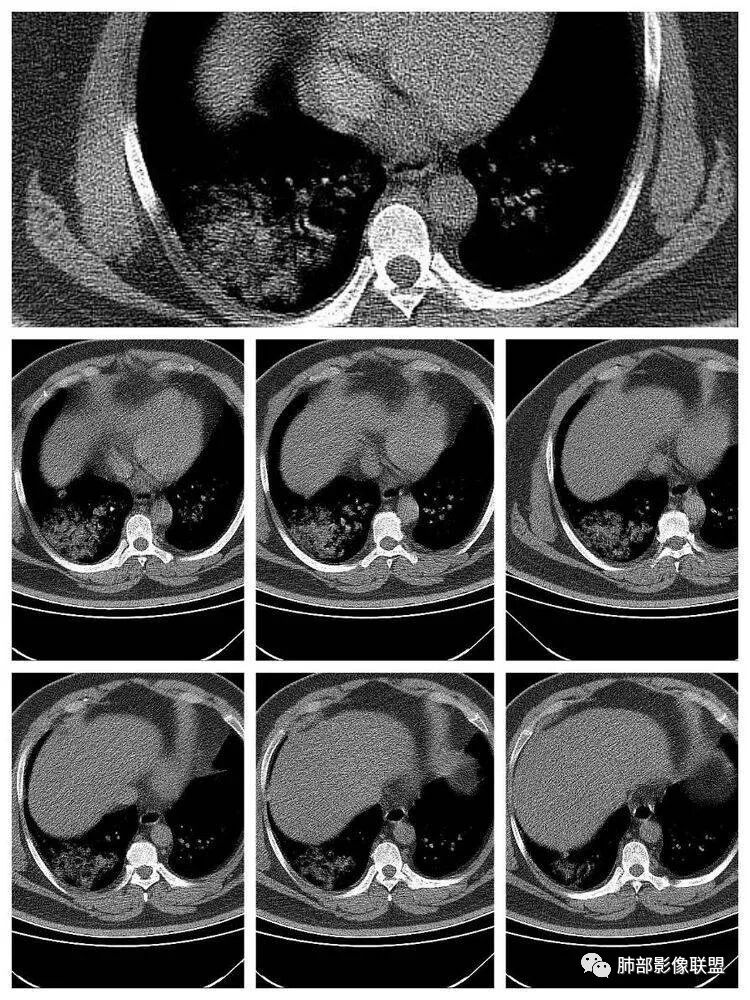

长沟流月去无声:第三点有意见这个人心脏大,左室供血很不好

南边:南边:不大啊冬瓜:熊老师不会考虑病毒感染,爆发性心肌炎吧南边:这个就不敢说淘时光:左心室心腔饱满,室间隔向右室侧有些移位,感觉左室有增大

长沟流月去无声:这个左室心肌都薄了南边:没有做增强啊长沟流月去无声:可以提示大家去看一下流感病毒性肺炎重症,WHO和卫生部都出过指南,建议你们仔细看看指南里危险人群一节,是哪几个

南边:1、感染:间质分布——病毒、支原体,支原体一般树芽征明显,累及小气道多,而且临床轻,不太支持2、血管炎,需要相关病史3、肺水肿:心脏不大,无胸水、无中央间质增厚、小叶间隔增厚,不太支持4、PAP,病史影像表现都不支持初学者:可能是病毒,但是好像并不是我们常见的流感病毒实变为主,腺病毒?就是太多灶了一点